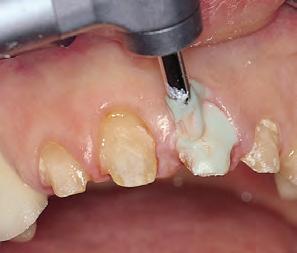

2. Give firm air/water spray to remove residual coagulum and to test for profound hemostasis. If bleeding continues, repeat.

3. After complete hemostasis has been attained, excellent retraction is achieved using Ultrapak™ knitted cord placed with the Ultrapak™ packer.

1. Well-healed tissue 2 weeks post-op.

Note: Perfect sulcular fluid control is mandatory if bonding and luting is adjacent to gingival sulcus.1